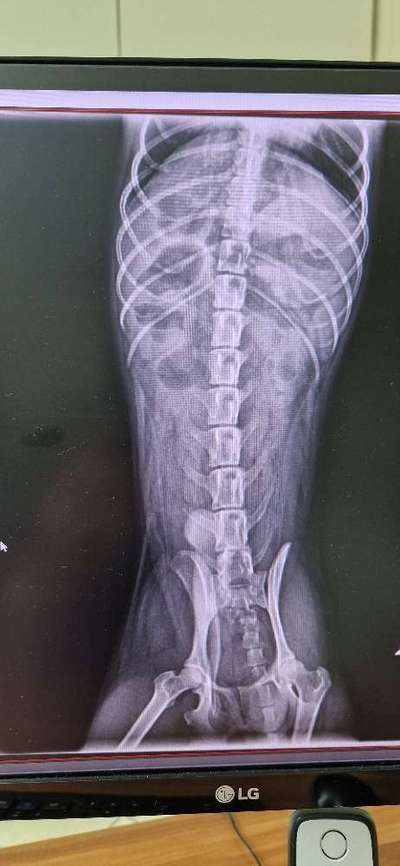

Wer kann mir helfen anhand der Bilder?? Mein kleiner flip hat sich nur noch erbrochen.

Er sagt Verstopfung, der kleine ist sei gestern abend in der tierklinik.

Wir drücken die Daumen das es der kleinen Fellnase schnell wieder besser geht. Hoffentlich keinen Darmverschluss. Und sie finden in der Tierklinik schnell die Ursache 🍀🍀🐕